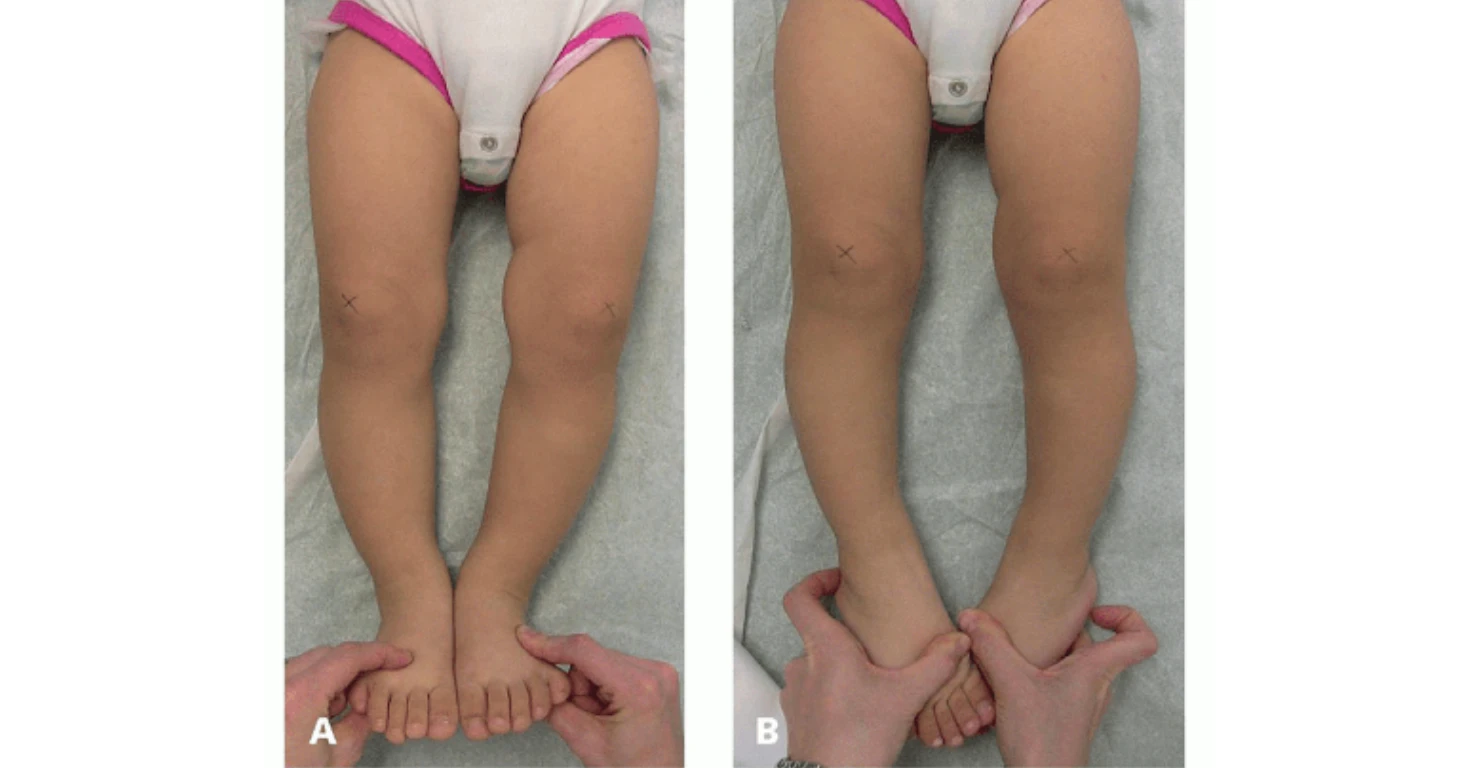

در کودکان و نوجوانان، چون استخوانها هنوز در حال رشد هستند، کفشهای استاندارد و اصلاحی میتوانند در برخی موارد به بهتر شدن فرم پا کمک کنند. اگر کودک از همان سنین پایین کفش درست بپوشد، این شانس وجود دارد که بدن خودش مسیر اصلاح را طی کند و فرم پا با گذشت زمان بهتر شود.

کفش مناسب برای کودکان با پای پرانتزی

انتخاب کفش برای کودکان اهمیت بسیار بالایی دارد، چرا که استخوانها و مفاصل آنها هنوز در حال رشد هستند و یک کفش نامناسب میتواند مشکلات جدی در آینده ایجاد کند.